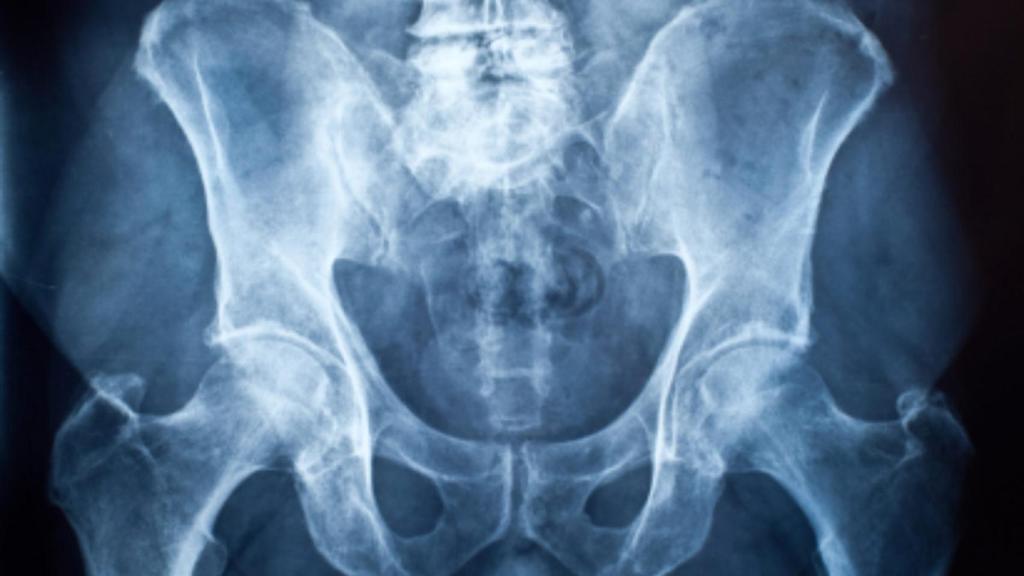

El esqueleto humano está compuesto por 206 huesos. Más de la mitad se encuentran en las manos y en los pies. Nuestro sistema musculoesquelético también se compone de músculos y tendones. En total, un ser humano tiene más de 650 músculos, que constituyen la mitad del peso corporal. El hueso más largo, fuerte y voluminoso es el fémur; y el más corto, el estribo, que forma parte del oído. Así, el sartorio es el músculo más largo, y el dorsal ancho, el más amplio. Al morirnos, el cartílago se descompone mucho más rápido que el hueso, de ahí que los cráneos de los esqueletos no tengan nariz ni orejas.